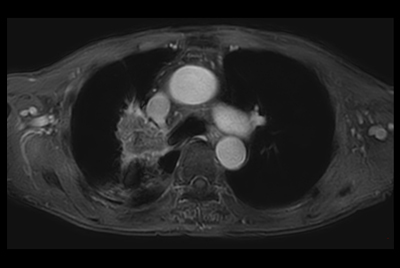

Thorax soft tissue lesion – Free breathing